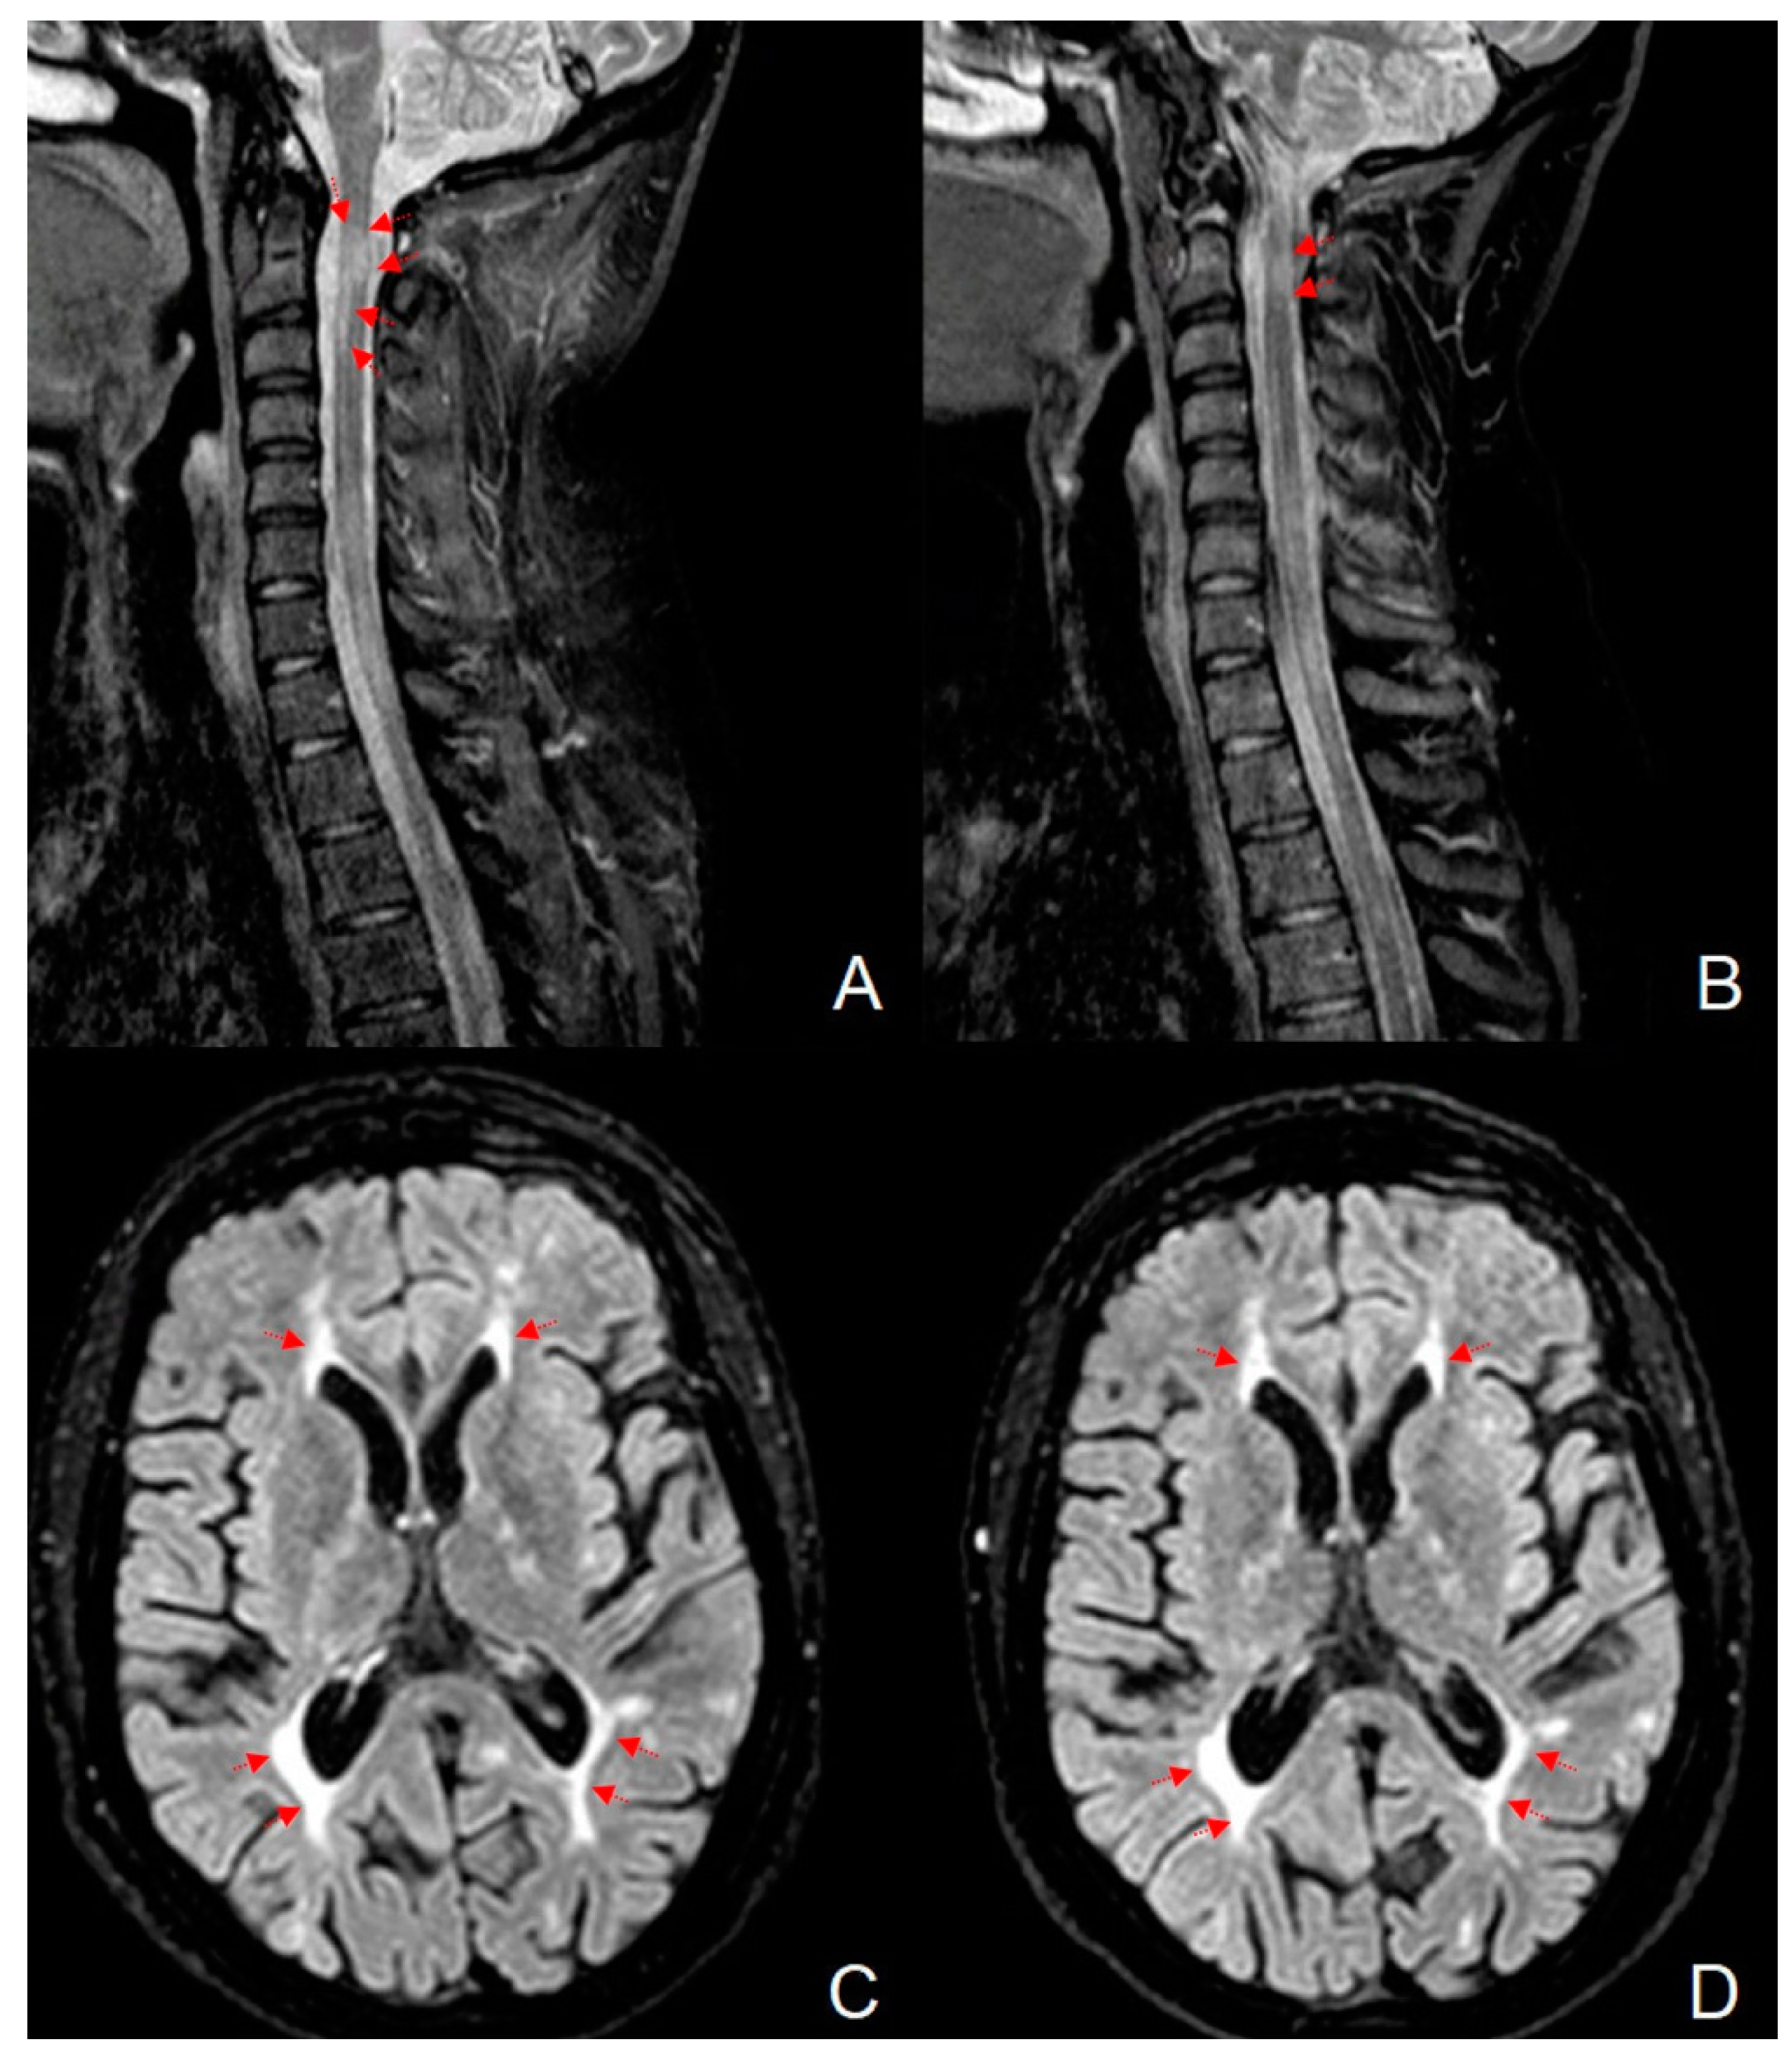

In July 2019, when the Fingolimod was ongoing for about one year, the patient had a brutal relapse starting with leg weakness that was treated initially by a total of 5 g of i.v. 6-MP. At the end of this treatment period, the EDSS 7.0 revealed severe lower-extremity weakness, with leg spasticity and ataxia, so we admitted her at the neurological department of the “F. Ferrari” Casarano Hospital. Here, after the MRI assessment, the patient underwent another brief treatment cycle of 3 g i.v. 6-MP without clinical improvement and we founded that the relapse was sustained by new T2-weighted cervical lesions, situated on C2–C3, and T5 levels (Figure 1A). These lesions did not evidence any contrast enhancement due to the 6-MP cycle performed at home before hospital admission.

Figure 1.

Magnetic resonance imaging on the short tau inversion recovery (STIR) sequence of the cervical spinal cord, affected by a demyelinating lesion at the second and third metamer before (A) and after (B) DFPP treatment. Note the reduction in the size of the lesion in comparison to the pre-treatment image. Axial brain magnetic resonance imaging on the fluid attenuated inversion recovery (FLAIR) sequence shows the periventricular lesion load before (C) and after (D) DFPP treatment. Red arrows evidence the brain and spinal cord lesions.

These lesions, partially confluent and not exceeding three metamers in length, were not associated with tumefactive cervical shape and fulfilled the radiological criteria for MS lesions, as expected. No new brain lesions were detected and a total intracranial volume (TIV) of 1328.8 mL was calculated using Siena software. Thus, the diagnosis of steroid-refractory relapsed MS on Fingolimod treatment was posed, DFPP therapy was indicated, and FTY was discontinued. In Figure 1C it could be also glimpsed two subcortical hyperintense left frontal areas, resulting from enhancing lesions at the disease onset. The demonstration of these lesions assumes an important diagnostic role in the present case, and they are better represented in Figure 2.

The control MRI performed before the department discharge showed detectable reduction in the volume of cervical lesions, as depicted in Figure 1B, but a stable brain lesion load (Figure 1D).